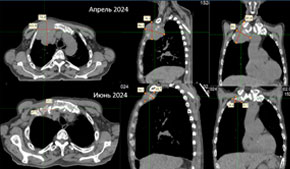

Пример адаптивной лучевой терапии при сленомегалии, обусловленной миелофиброзом. Регресс объема селезенки – 50% к седьмому сеансу. |